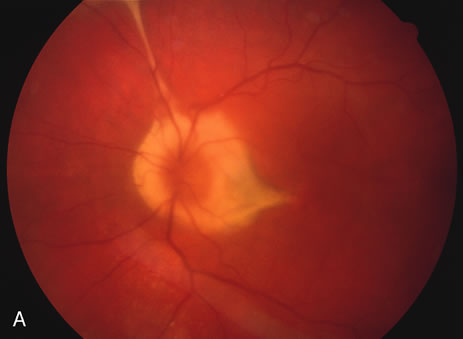

Some patients present with subretinal bands that extend between chorioretinal scars. In addition there may be initial active yellow choroidal lesions that subsequently become atrophic. Vitreous cells are usually present although they may be few and difficult to detect. Visual acuity loss in these cases may be due to active choroidal neovascularization, subretinal bands under the fovea, or from cystoid macular edema. The vast majority of affected patients are women with a mean age of 27 years and both eyes are usually involved. The affected individuals tend to be myopic.49 The age range is from 6 years to 76 years and there is no racial predilection.40 Whether it is a separate disease or a more severe form of multifocal choroiditis is controversial (Figs. 10 and 11). Aggressive therapy is warranted because it has a poorer prognosis than most cases of multifocal choroiditis. This syndrome has been called either diffuse subretinal fibrosis or progressive subretinal fibrosis syndrome.

Fig. 10. A. Fundus photograph showing the subretinal fibrosis extending from the disc to the periphery in a case of diffuse subretinal fibrosis. B. Fundus photograph showing the marked fibrosis in the midperiphery. C. Multifocal choroiditis type lesions noted in the inferior retina.